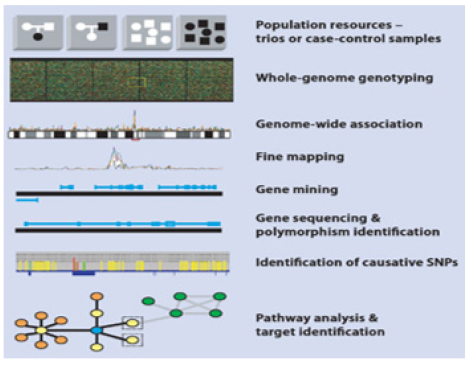

Disease risk assessment could be defined as the systematic evaluation and identification of Risk Factors (Figure 10) responsible for a disease, estimation of risk levels and finding possible ways to counter the onset and progression of a disease or a cancer within the population.